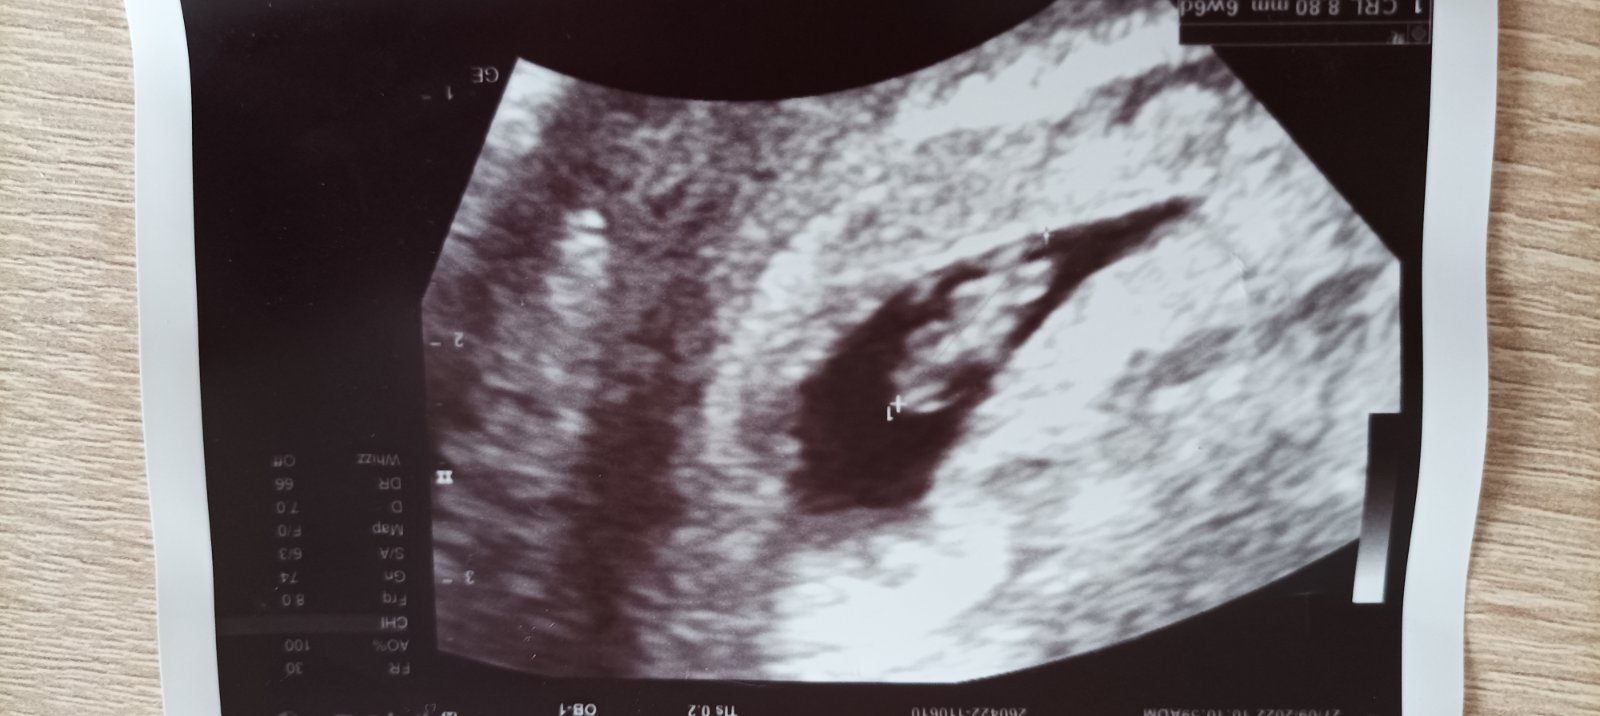

Ahoj těhulky, hlásím se po kontrole 8+6, podle ultrazvuku 8+3. Srdíčko stále funguje a drobeček roste jak má. Jak se cítíte? Mě konečně přestaly bolet prsa, dokonce i s únavou je to lepší, a kromě zhoršeného exému si nemůžu na nic ztěžovat.